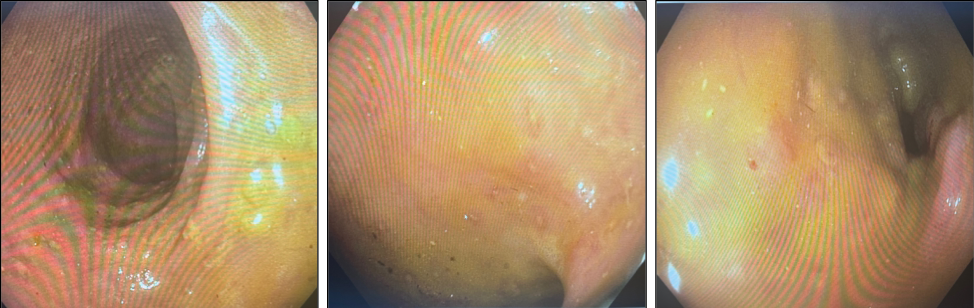

Images from flexible sigmoidoscopy showing shallow ulcerations in sigmoid colon

Histologic slides with Steiner stain identifying a large volume of spirochetes at the mucosal edge of the bowel.